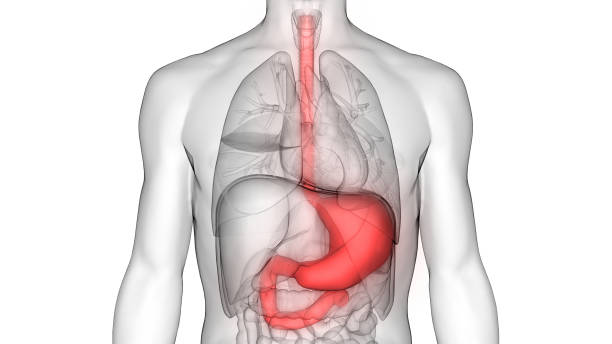

섭취물 역류

식도내의 역류 현상을 의미합니다. 일반적으로, 식도는 식후 3시간 이내에 비어있는 상태를 유지하고 있지만, 섭취물 역류가 발생하면 위에서 소화액과 음식물이 다시 식도로 역류하여 염증과 손상을 유발할 수 있습니다. 이러한 섭취물 역류는 식도암의 위험 요인 중 하나입니다.

속쓰림

속쓰림은 위산이 식도로 역류되어 식도를 자극하면서 생기는 통증을 말합니다. 위산은 위에서 식도쪽으로 역류하게 되면서 식도 점막을 자극하고 손상시키기 때문에 식도암의 발생 위험도를 증가시킵니다.